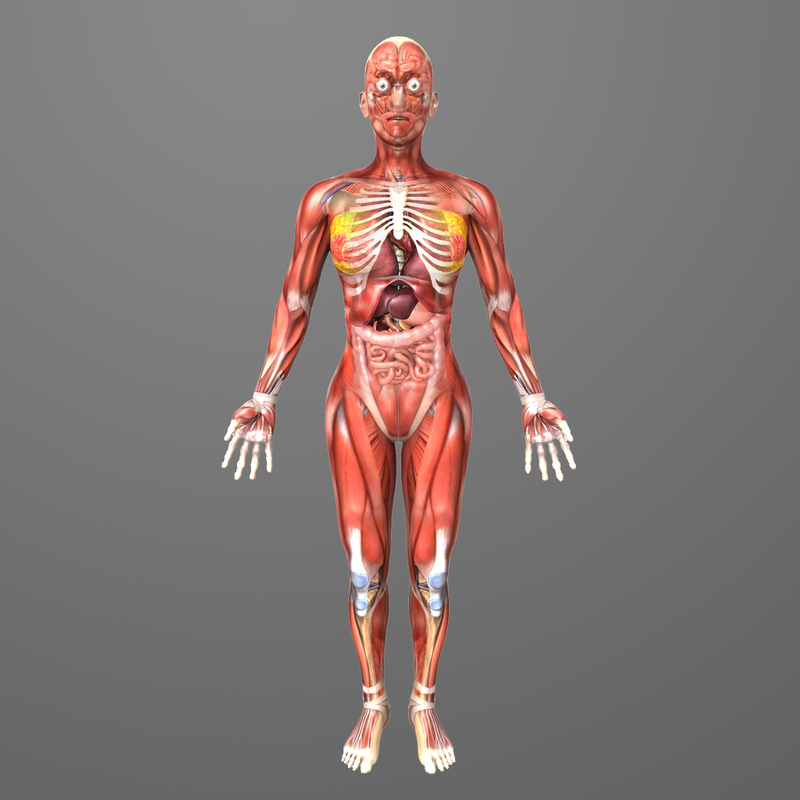

Human Female Anatomy – Body Muscles Skelet… 3D Model .max .obj .3ds …

human female anatomy body 3d model